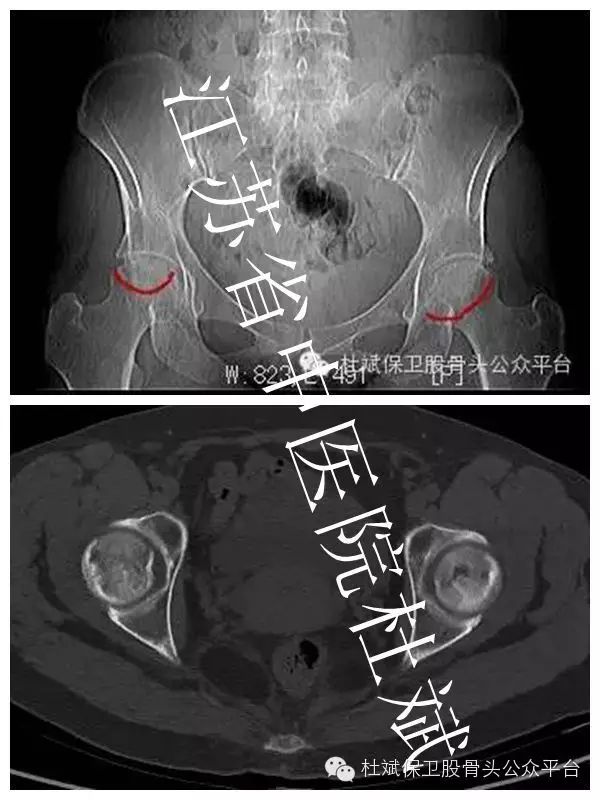

全面恢复股骨头供血是成功保髋核心关键